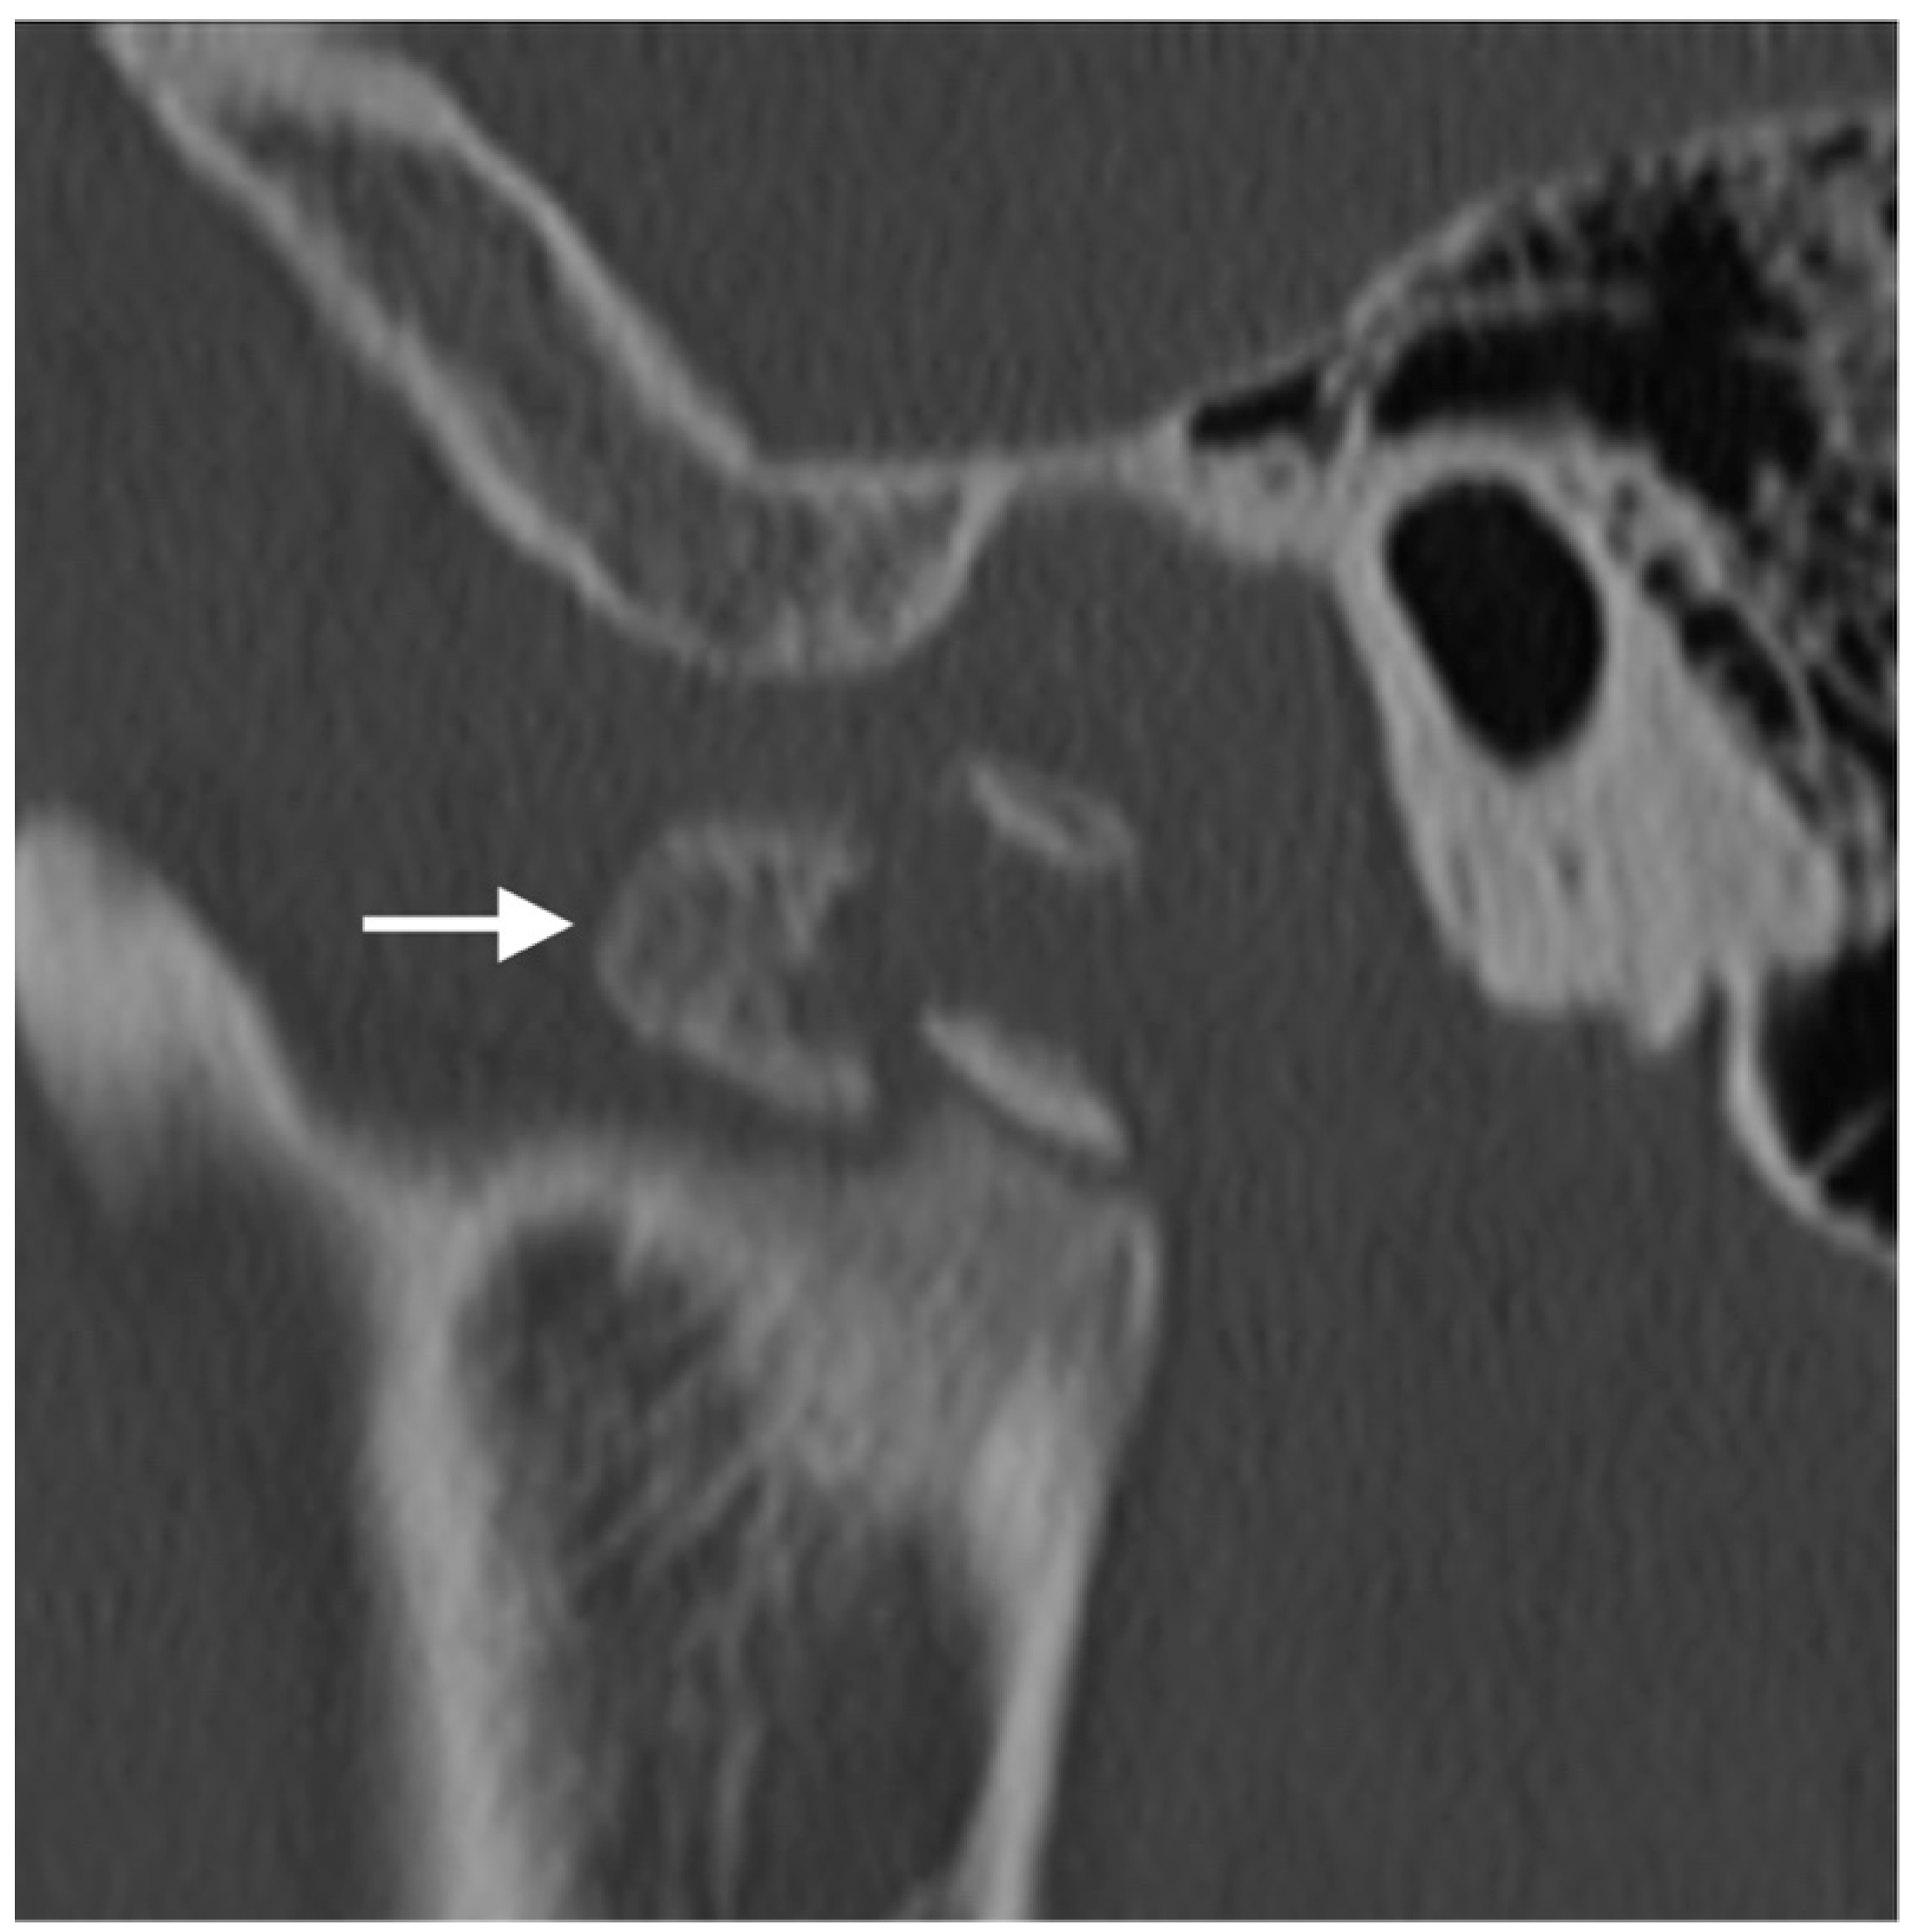

Figure 8. Trauma. Sagittal CT image of the TMJ demonstrates comminuted fracture of the condylar neck with a displacement of the fracture fragments. Mild sclerosis around the fracture lines suggests a component of interval healing. The tip of the mandibular condyle (arrow) is displaced antero-inferiorly.

In patients with a condylar fracture, the unopposed force of the lateral pterygoid muscle usually causes inferior and anteromedial dislocation of the condylar head and the lateral displacement and telescoping of the ramus (Figure 8). Multidetector CT is the modality of choice for evaluating facial and mandibular fractures in the acute setting. Most condylar fractures will show functionally favorable outcomes after closed reduction. However, traumatic dislocation of the disc or injury to the retrodiscal soft tissue can lead to joint ankylosis, a devastating complication. Studies have shown a correlation between the severity and pattern of condylar fractures on CT and risk of soft tissue injuries. However, MRI is the modality of choice to evaluate retrodiscal tissue injury and disc dislocation [42,43].